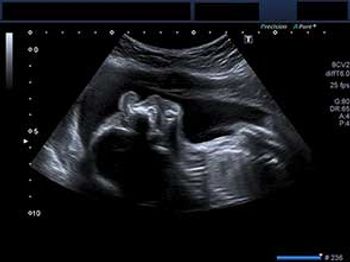

What is your diagnosis of this major pathology in a second trimester fetus?